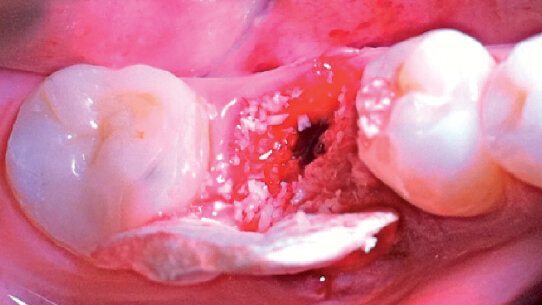

Eseguita l’estrazione atraumatica separando le radici, si riscontra l’effetivo minus osseo e si procede allo scollamento intorno ai margini dell’alveolo senza traumatizzare e lacerare le papille (Figg. 2a, b, c). Successivamente si posiziona l’impianto in modo protesicamente guidato (Way Milano 5,5 mm per 10 mm di altezza con superficie Syntegra – Geass srl), e si colma l’alveolo con un biomateriale eterologo (OX Bioteck®). La matrice di collagene viene modellata con due alette. La prima ovale che fungerà da tappo, la seconda avrà un corpo ovale e due alette che si infileranno tra il periostio scollato e l’osso.

L’ala vestibolare andrà anche a chiudere il difetto, a livello della radice mesiale, valutato al sondaggio (Figg. 3a, b, 4). La matrice viene stabilizzata con una sutura (Fig. 5). La guarigione a sette giorni (Figg. 6a, b), sembra mostrare una recessione dei tessuti molli, invece se si osserva attentamente si può notare un fronte di tessuto molle sta invadendo, arrampicandosi, la porzione superiore della matrice. Questo fenomeno è ancora più evidente a 15 giorni (Figg. 7a, b). Senza intervenire più a 3 mesi, otteniamo un’ottima qualità e quantità di tessuto molle intorno al nostro impianto (Figg. 8a, b).